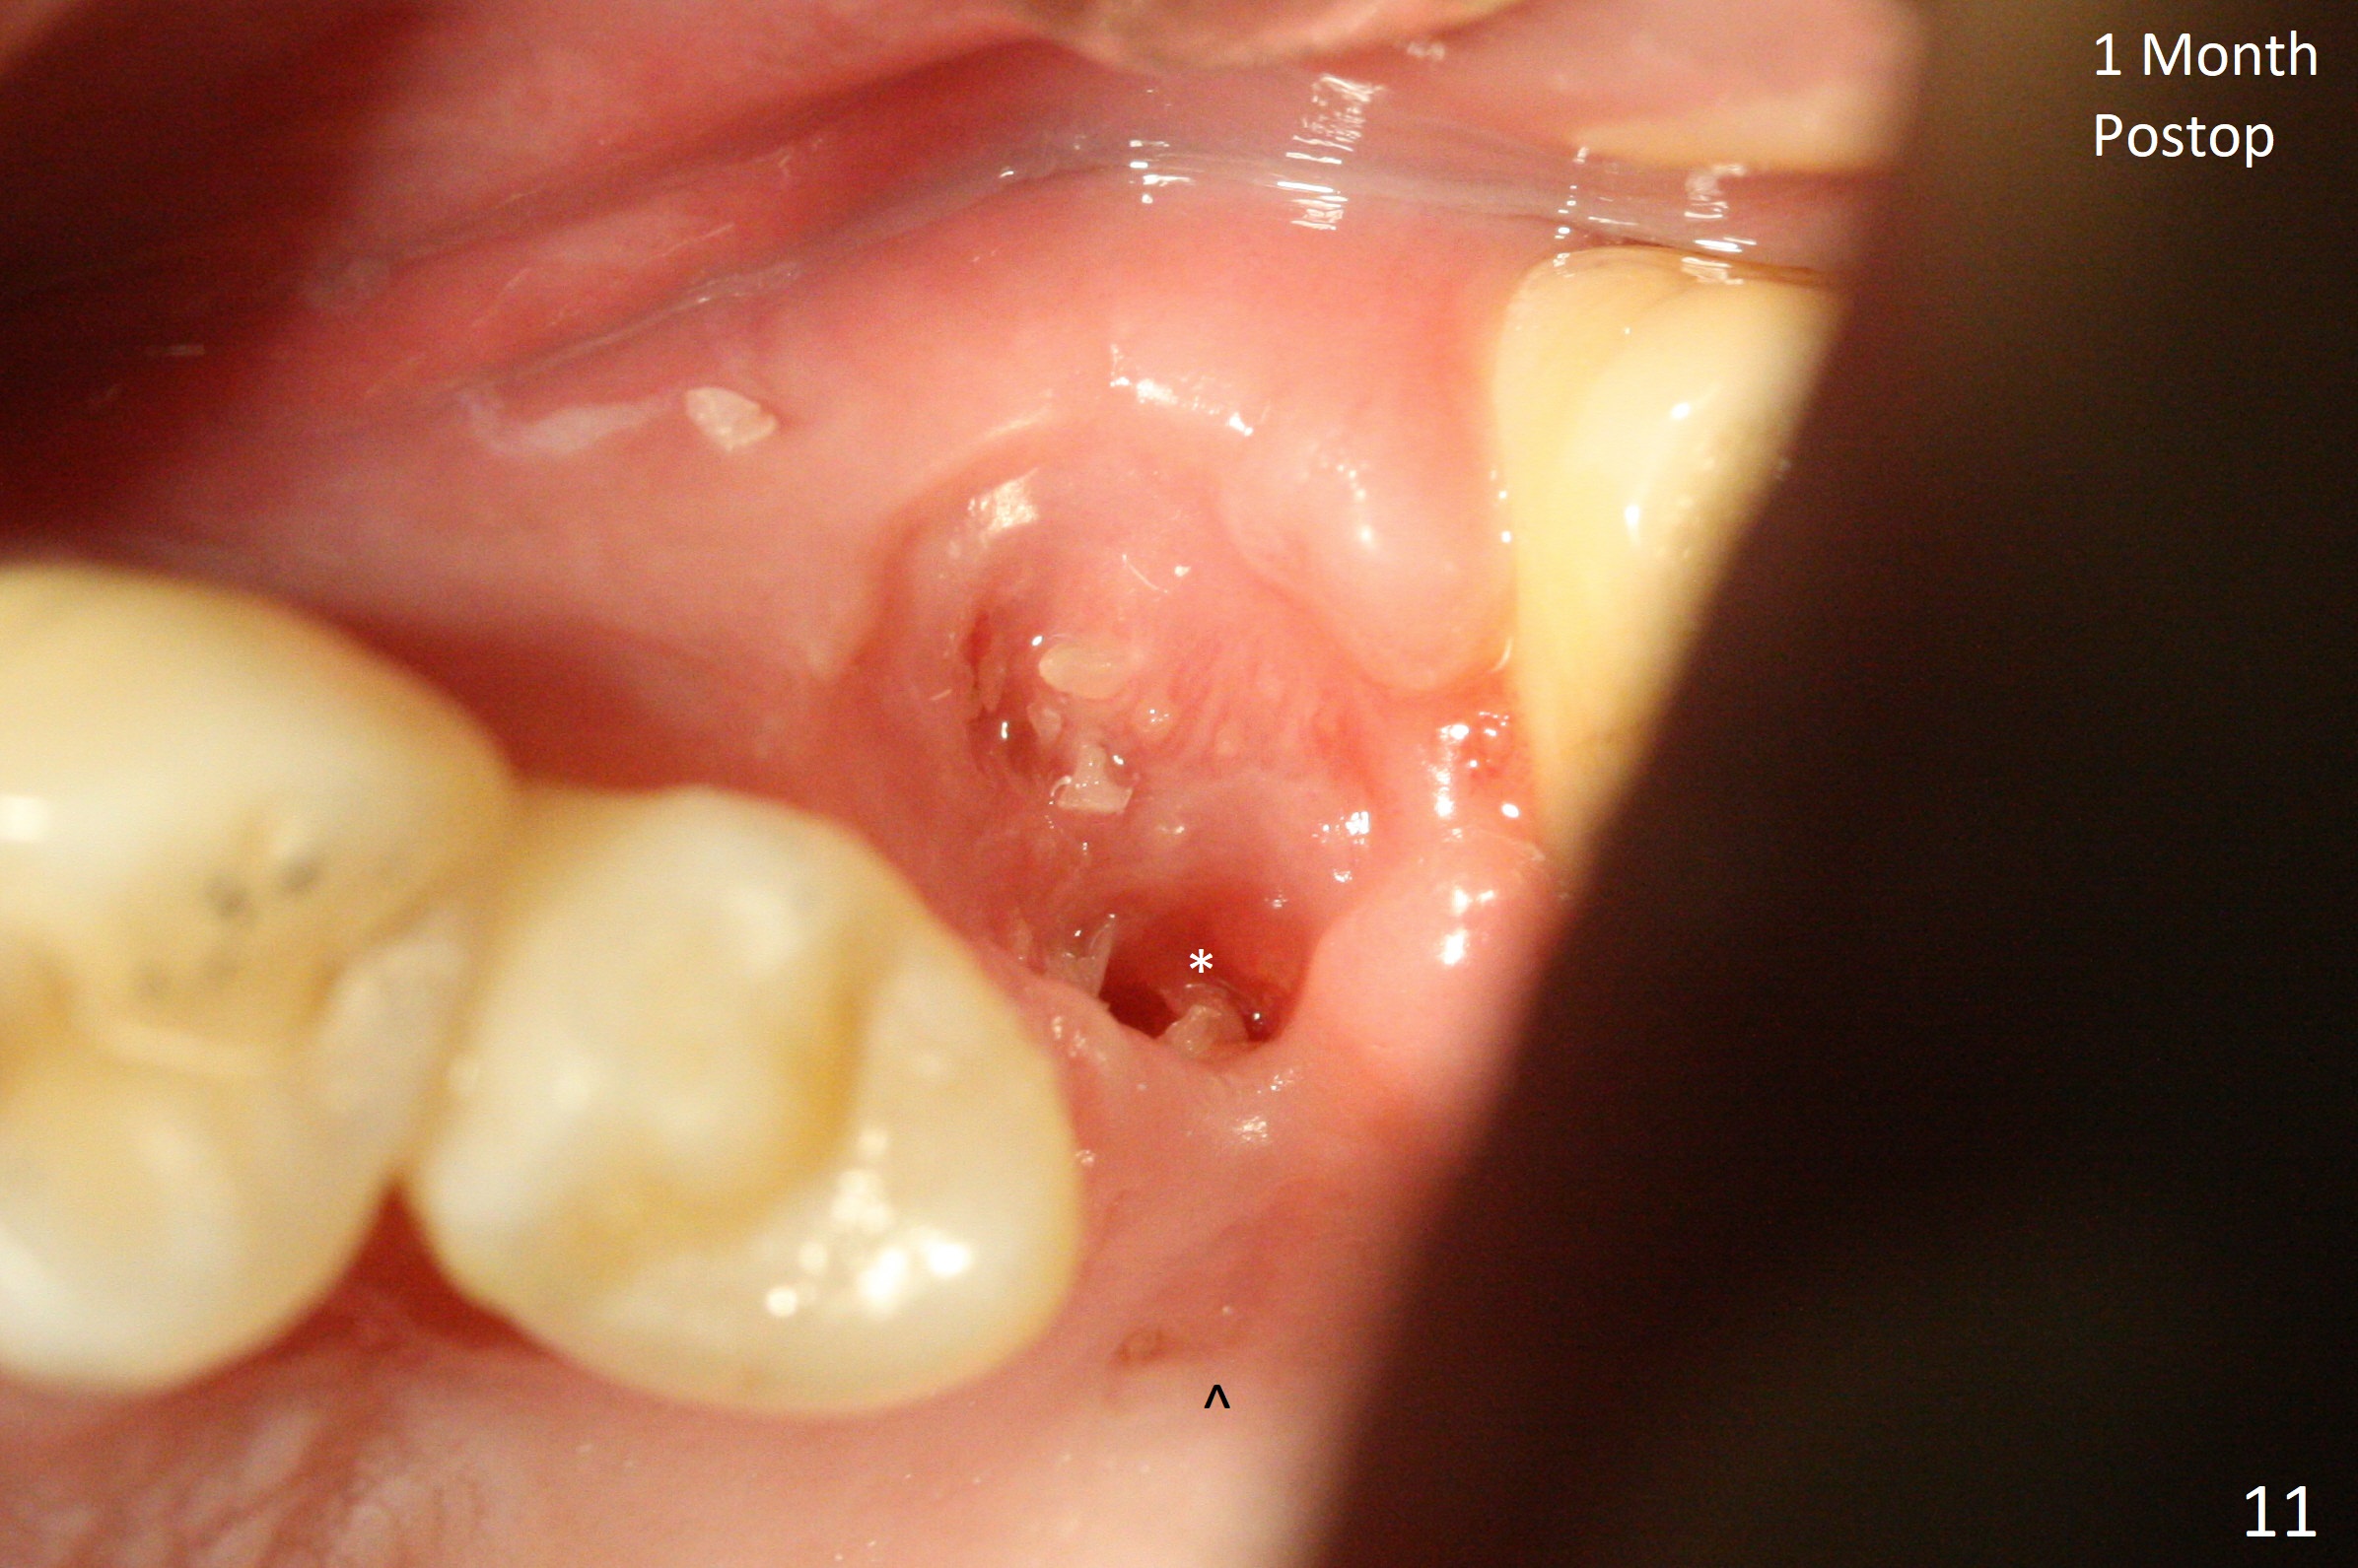

A 29-year-old man has pain in the upper left quadrant. It appears that the tooth #14 has endo and post failure with palatal fistula (Fig.1,2). The septum is almost non-existent; the palatal wall is low, while the sinus floor is present. Sticky bone is placed first against the defective palatal wall and presumably pushed as high as to the sinus floor (Fig.3-5). PRF plug/membrane and 6-month membrane are used to close the socket with 4-0 Chromic gut suture apparently securely, followed by periodontal dressing. Examination of the extracted tooth shows granulation tissue between the roots (Fig.6 *). Underneath the granulation tissue is cement-like material (Fig.7 C). Distal-to-mesial X-ray examination shows possible furcation perforation (Fig.8 *), while mesial-to-distal one the cement-like material in the furca and pulpal chamber as well as MB2 (Fig.9 >). The patient returns 8 days postop, reporting pain reduction, but wants to have #16 extracted. The periodontal dressing is loose, but stuck with 2 sutures underneath. When the dressing is removed, the wound looks normal (Fig.10). In fact the dressing is re-applied. The 6-month membrane has lost 1 month postop. The majority of the socket heals except the palatal (Fig.11 *), as related to the existing palatal fistula/defect (^). Orthodontics is being considered. If the buccal plate collapses 4.5 months post extraction, socket shield should have been done. In fact the buccal plate is robotic, while the bone density is low palatal in CT (Fig.12).